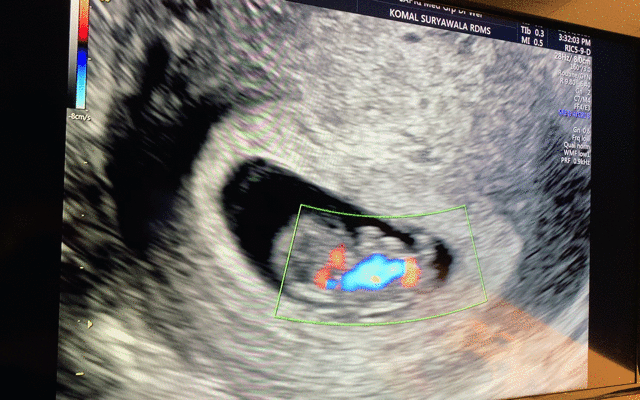

그렇게 튼튼이 모습을 별 설명 없이 보여주셨는데, 움직이길래 '움직인거에요?' 했다. 그러고나서는 감격에 벅차 눈물이 차올랐.. 다기 보다는, '오, 잘 살아있구나' 하는 생각이 들었다. 남편도 보아하니 감격보다는 신기함이 더 큰 것 같았다. 나중에 지나고나서 물어보니, SF 영화에서 보는 외계인 검사 장면ㅋㅋㅋㅋ-_- 같았다고 한다. 아기는 주수에 맞게 잘 크고 있다고 했다. 그리고나서 보여주신 아기 심장 뛰는 모습! 이때 '열심히 자라주고 있구나!' 하는 생각과 함께 책임감이 들면서 조금 뭉클했다. 우리는 이렇게 심장 소리는 듣지 못하고, 보기만 했다. :)

요란하게 뛰고 있는 튼튼이 심장 박동 모습